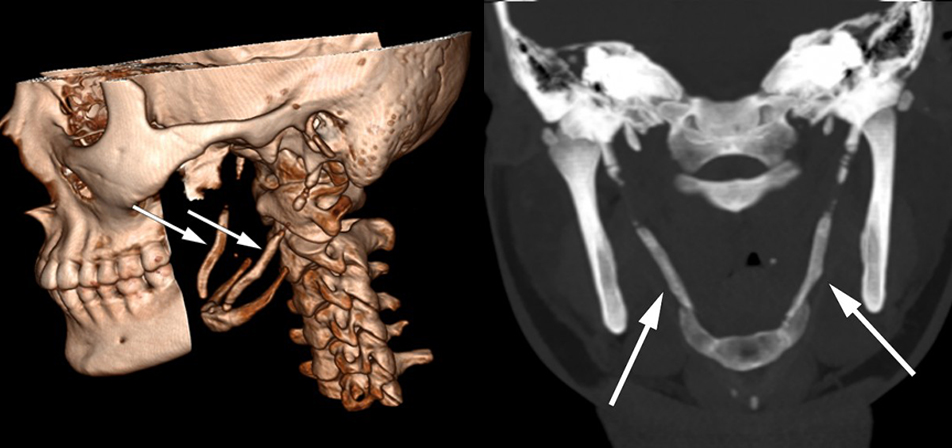

Symptomene ble fremprovosert og forverret med sidebøy og rotasjon av hodet mot høyre. Anamnestisk hadde hun hatt en lignende og forbigående episode to år tidligere. Det var ikke noe hode- eller nakketraume i sykehistorien. Klinisk undersøkelse var upåfallende, foruten palpasjonsømhet peritonsillært og over venstre nakkehalvdel. Omfattende utredning med nevrofysiologiske, bildediagnostiske og øre-nese-hals-undersøkelser viste normale funn. CT-undersøkelse av nakken avdekket forkalkning i ligamentum stylohyoideum bilateralt (se piler), noe som kunne forklare pasientens symptomer.